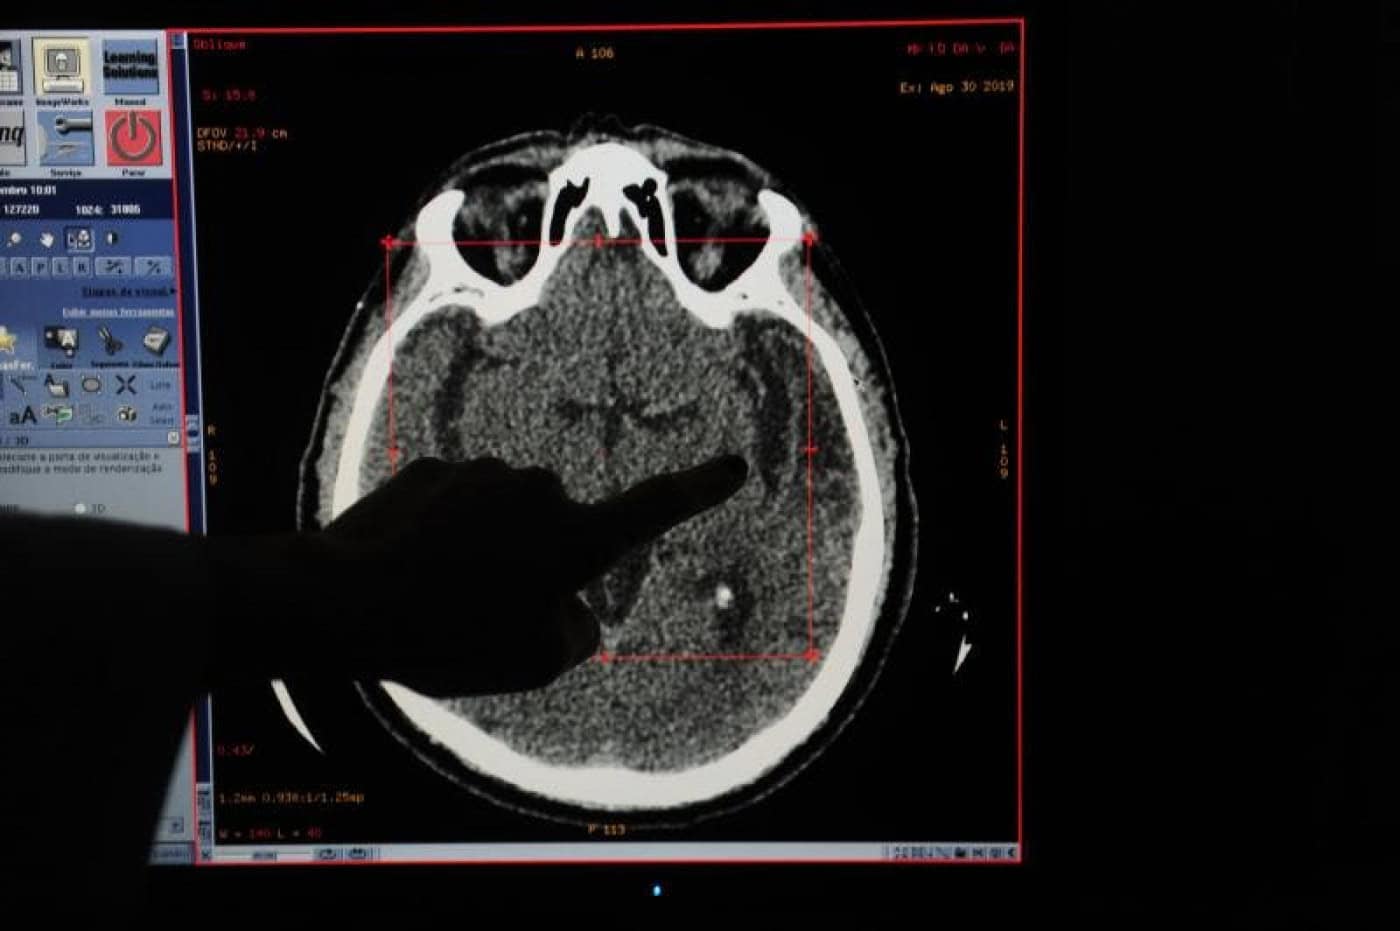

Neste Dia Nacional do Doente com AVC, maior causa de incapacidade e morte no nosso país, a RUM conversou com o presidente da Portugal AVC, António Conceição, que alerta para a falta de acompanhamento dos doentes que podem contribuir para novos episódios de AVC ou outras complicações de saúde.

Para o responsável outro dos efeitos da pandemia é a quebra de idas ao hospital em caso de AVC. “Muitos fazem-no numa fase tardia o que aumenta a gravidade da situação”, garante.

Por ano, existem cerca de 25 mil episódios de internamento de doentes com Acidente Vascular Cerebral. Em média, morrem em Portugal 30 pessoas com AVC. São 11 mil óbitos por ano.